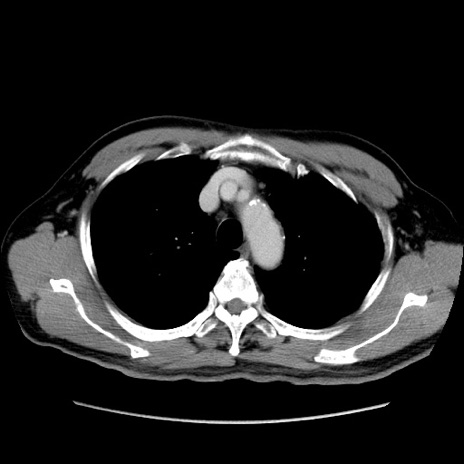

症例34(横断像)

【症例】60歳代 男性

【主訴】右鼠径部膨隆

【現病歴】1年程前より右鼠径部膨隆あり。自己にて還納可能だったため放置していた。3時間前より右鼠径部の脱出を認め、還納困難となり受診。

【既往歴】高血圧

【身体所見】右鼠径部に小児頭大の膨隆あり。弾性硬であり、用手還納は困難。左鼠径部にも膨隆を認める。脱出はなし。

【データ】WBC 15500、CRP 測定なし